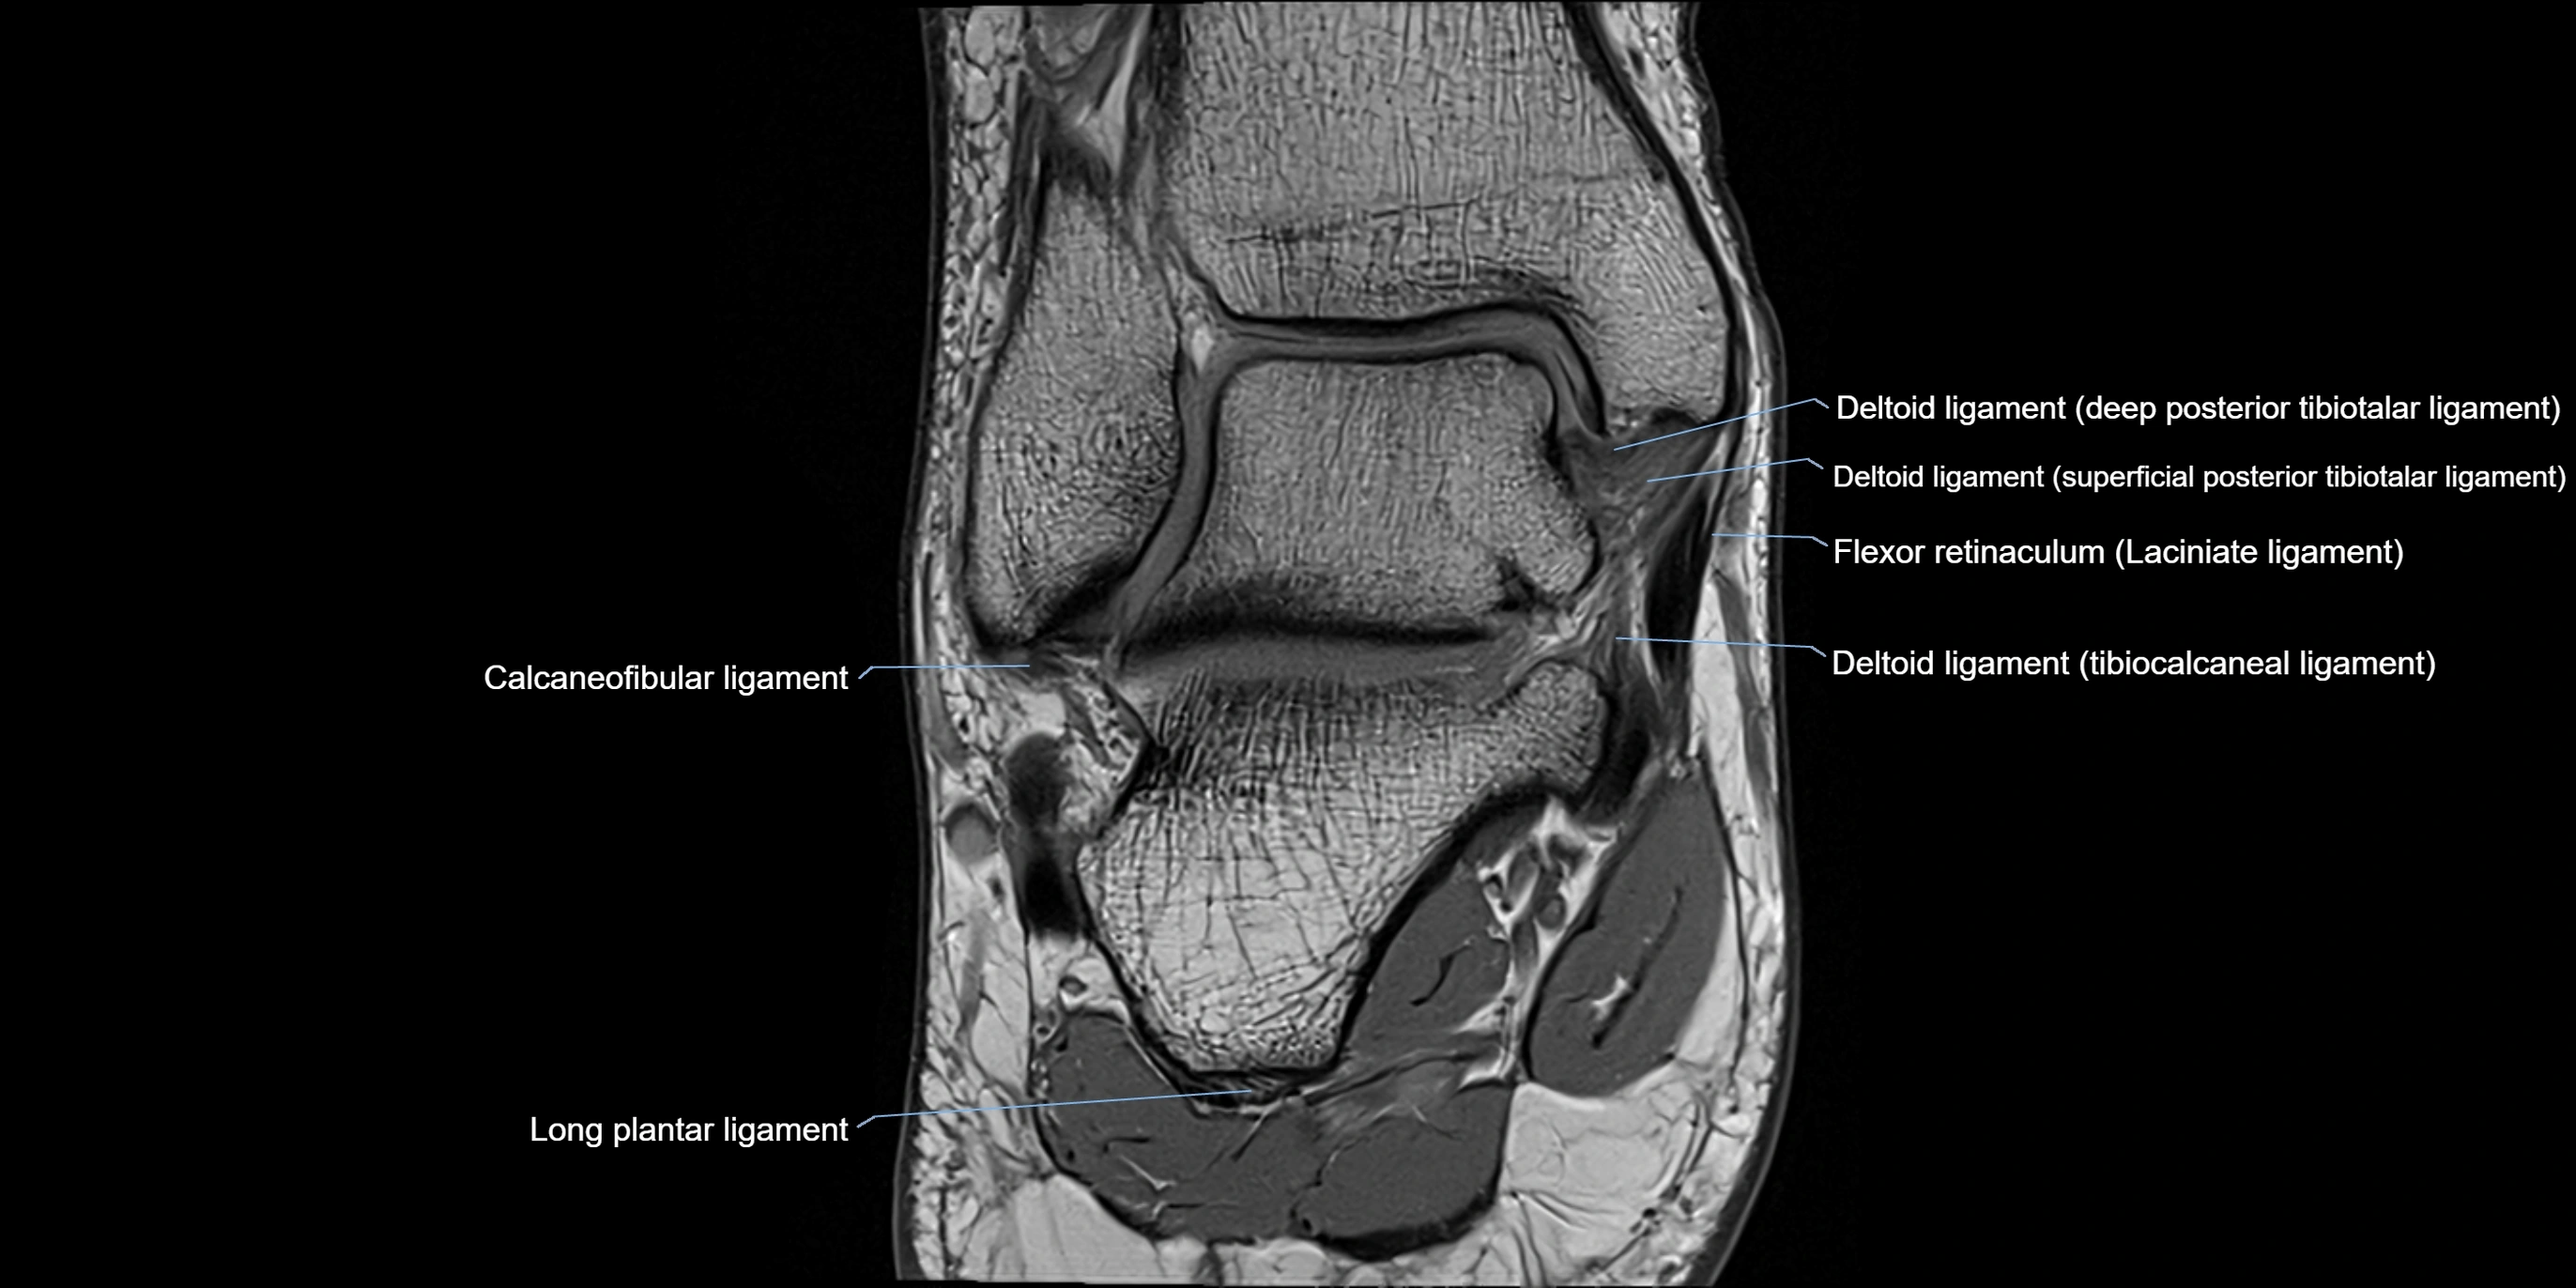

MRI image

image